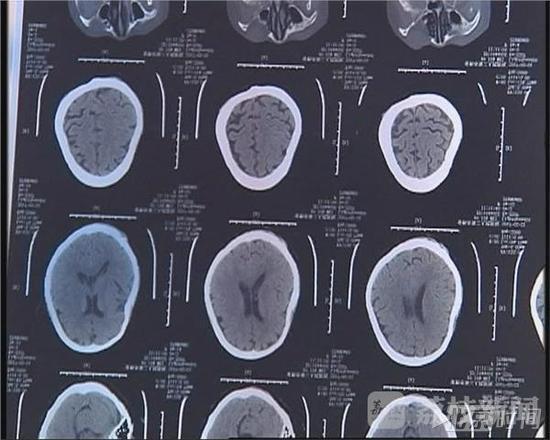

人今年67岁,有两个儿子。2月21日上午,徐金妹因琐事和大儿子发生口角,之后,她的大儿子对她大打出手。